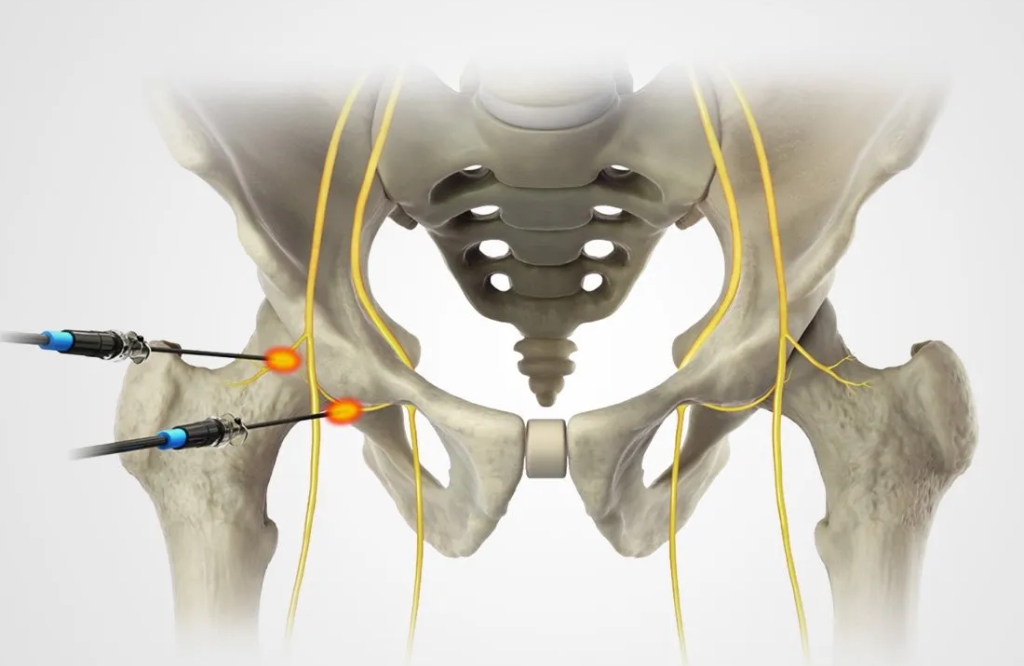

O bloqueio de nervo é um procedimento minimamente invasivo utilizado para o alívio rápido e eficaz da dor crônica. A técnica consiste na aplicação de anestésicos e anti-inflamatórios diretamente nos nervos responsáveis pela dor, reduzindo a sensibilidade da região afetada e proporcionando mais conforto ao paciente.

Essa abordagem é especialmente indicada para pacientes que sofrem com dores na coluna, hérnias de disco, neuralgias, síndrome do túnel do carpo e dores articulares crônicas, condições que comprometem a mobilidade e impactam a qualidade de vida. Com esse tratamento, é possível reduzir o uso de analgésicos, evitar procedimentos cirúrgicos e restaurar o bem-estar.

Os bloqueios são personalizados conforme a necessidade de cada paciente e podem ser utilizados como alternativa para evitar cirurgias ou como parte de um tratamento multidisciplinar. Além disso, os efeitos podem ser duradouros, permitindo um retorno mais rápido às atividades normais.